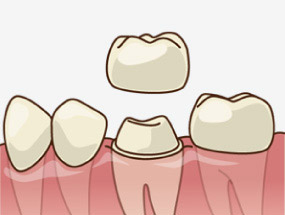

クラウンは、虫歯を削った後に被せる人工の歯のことで、「差し歯」や「被せ物」と言われています。比較的小さな虫歯の場合はインレー(詰め物)による治療を行いますが、大きな虫歯や根管治療(神経を取る)をした後は、詰め物ではなくクラウン(被せ物)による治療となります。

コアとは、クラウン(被せ物)を被せるための土台に当たります。この部分が歯の中に差し込まれるカタチになるので「差し歯」の由来となっています。

神経を失った歯は脆くなってしまうので、コアと呼ばれる土台を差し込み、補強した上で、被せ物をします。また、神経がなくなると、神経が通っていた部分は空洞になるため、また細菌感染が起こらないよう、樹脂とコアで密閉することで、二次感染を防ぐという効果も担っています。